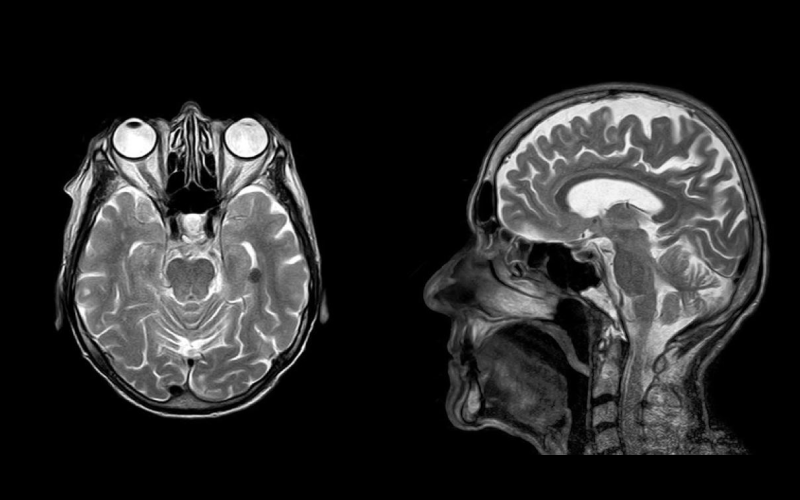

Un nuevo malware de escáner tomográfico y resonancia magnética es capaz de modificar los resultados, haciendo creer a los médicos que tenemos cáncer.

Los escáneres de tomografía y de imagen por resonancia magnética son valiosas herramientas para comprender mejor el interior de nuestro cuerpo. Ofrecen grandes ventajas respecto a un escáner de rayos X convencional. Como la posibilidad de obtener imágenes en todos los ángulos posibles en el caso de las tomografías; o la de obtener imágenes secuenciales en secciones del cuerpo en el caso de la resonancia magnética.

Estas imágenes son muy útiles, especialmente para descubrir tumores cancerígenos. Pueden ser vitales para comprender mejor la localización y el alcance del cáncer, para conseguir el mejor diagnóstico y por lo tanto, el tratamiento adecuado. Aunque a veces es normal encontrarse con artefactos visuales en estas pruebas (sobre todo si el paciente se ha movido), suelen ser bastante fiables.

Sin embargo, los modernos aparatos usados para realizar estas radiografías están conectados a la red del hospital para poder enviar los datos a un ordenador cercano; y por lo tanto, son susceptibles a ataques de hackers, como ha demostrado unos investigadores israelíes, que han desarrollado un malware especialmente diseñado para atacar este tipo de escáneres CT (tomográficos) y MRI (de resonancia magnética).

Los investigadores querían demostrar lo vulnerables que son estos aparatos médicos normalmente, y lo efectivos que pueden ser los ataques a la red del hospital. Para ello, desarrollaron un malware que es capaz de modificar los resultados de estos escáneres para incluir falsos tumores cancerígenos; las imágenes resultantes eran modificadas de tal forma que no fuesen sospechosas para los médicos.

En las pruebas se demostró que estas radiografías modificadas eran capaces de engañar a todos los radiólogos; en las imágenes modificadas, los médicos presentaron un diagnóstico de cáncer el 99% de las ocasiones. Lo llamativo es que, incluso cuando les avisaban de que una imagen había sido modificada, el 60% de las ocasiones seguían creyendo que eran tumores reales.

También sirve para eliminar tumores de las radiografías

Que te diagnostiquen cáncer sin tenerlo ya es lo suficientemente malo, pero peor aún es que también funciona al contrario. El malware también es capaz de eliminar la presencia de tumores en las radiografías, y el 94% de las ocasiones los médicos afirmaron que el paciente estaba sano; si les avisaban de que las imágenes habían sido modificadas, el 87% de las veces no creían que el paciente tuviese cáncer, cuando en realidad sí lo tenía. Hasta el software usado para detectar tumores fue engañado de esta manera.

Este malware no ha sido publicado, y no hay indicios de que se esté usando en ataques contra hospitales; pero demuestra el gran problema de seguridad de los hospitales modernos, y que, en teoría, es perfectamente posible modificar los resultados de estas pruebas sin que nadie se de cuenta.